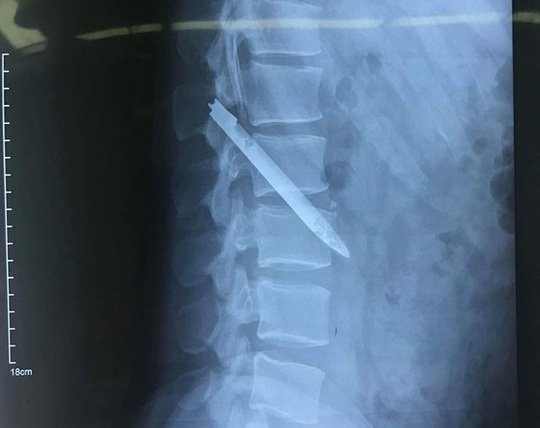

Lưỡi dao dài 13 cm nằm trong cơ thể chiến sĩ công an suốt 11 năm

Xã hội - 21/04/2018 15:00

Khi bệnh nhân là một chiến sĩ công an nhập viện với triệu chứng đau ở lưng, các bác sĩ đã khám, chụp X quang...